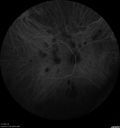

31 year old man with vision loss in the right eye more than the left eye. He has an anaplastic astrocytoma diagnosed 10/2017 the first one was 10/2014. These are different locations. They are treating them with Chemotherapy and Avastin. It might be that one might have spread from the other. He was clean for 3 years. He is on Avastin and Temozolomide but his blood counts have been good. December 2017 he had a herpes superficial infection in the right eye which responded to treatment. The last neurosurgery was October 2017. Going to Duke June 5 and seeing a neuroophthalmologist there. VA OD: Dcc20/40 PH20/25 NccJ5 VA OS: Dcc20/16 PH20/10 NccJ1+ His fundus is presumably nocardia, pneumocystis, aspergillis or cryptococcus. His LP was negative and he was tried on a course of antifungals. He was then lost to followup

Multifocal Choroiditis - Pneumocystis - aspergillis - cryptococcus671 views31 year old male with anaplastic astrocytoma on chemotherapy with mild vision loss in the right eye. LP did not reveal organism. He was placed on a trial of anti-fungal medications and lost to follow-up00000